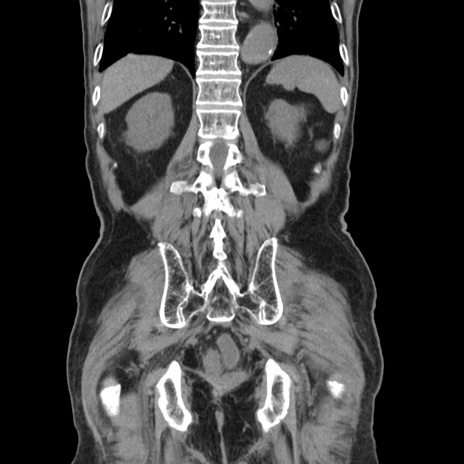

症例24(冠状断像)

【症例】80歳代男性

【主訴】左側腹部痛、嘔吐

【現病歴】本日早朝より左腹部に痛みあり。昼頃嘔吐認めたため、救急要請。

【既往歴】直腸癌(Mile手術)、胆摘

【身体所見】意識清明、BT 35.9℃、BP 221/93mmHg、SpO2 97%(RA) 、腹部:左ストーマ周囲に限局性の腹部膨隆あり。 膨隆部自発痛・圧痛あり・軟。

【データ】WBC 7700、CRP 0.09